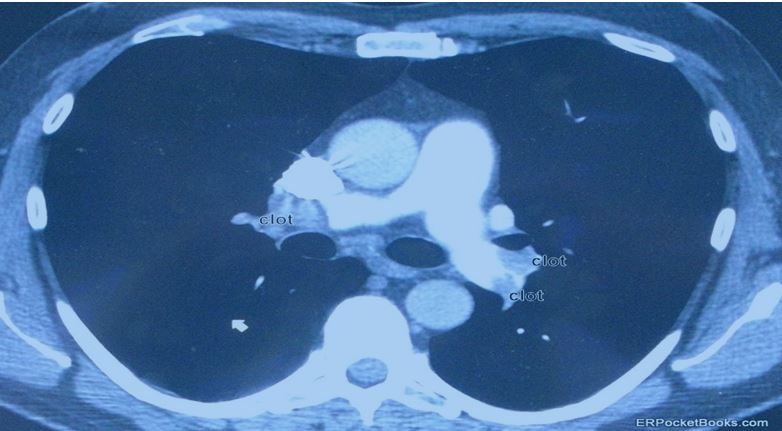

Figure 3. CT scan of the chest.

A subsequent chest CT scan (Figure 3) shows large clots in both main pulmonary arteries. This presentation would be somewhat atypical for unstable angina, since there is no chest discomfort. Dyspnea alone without any chest pain is not that atypical for a large PE, since the pain from a PE is thought to be the result of lung infarction, which is actually more common with smaller PEs. See Table below for more pitfalls in the diagnosis and management of PE.